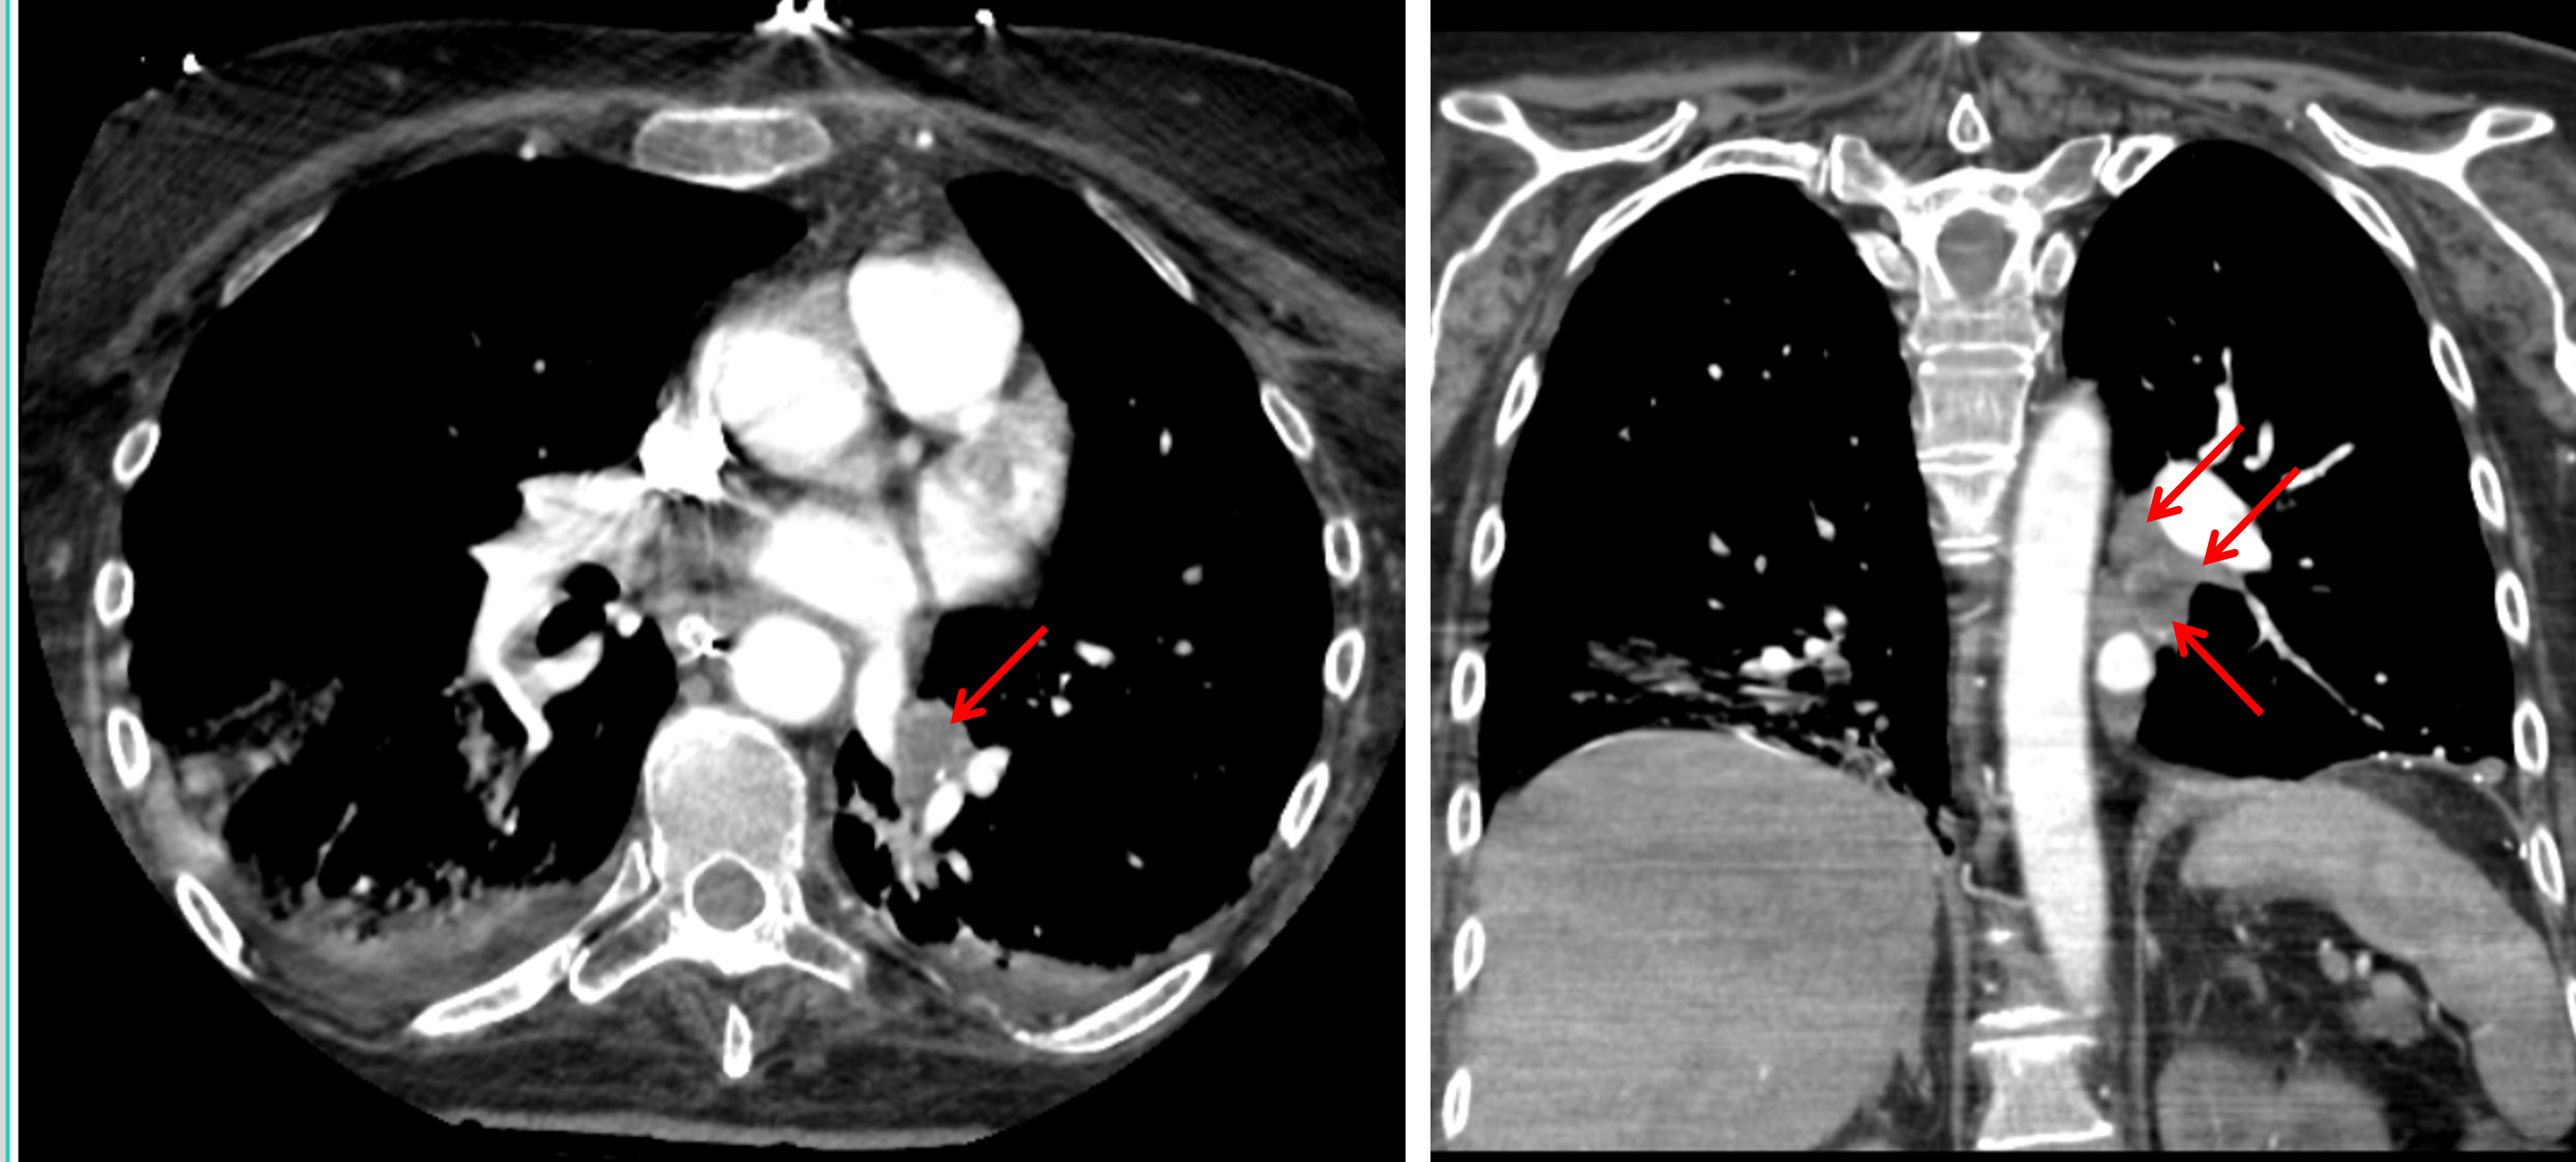

Indication: Acute respiratory failure

CT

Sample ReportFindings consistent with massive aspiration.

Age-indeterminate T9 compression fracture without bony retropulsion. Recommend correlation with point tenderness at this location.